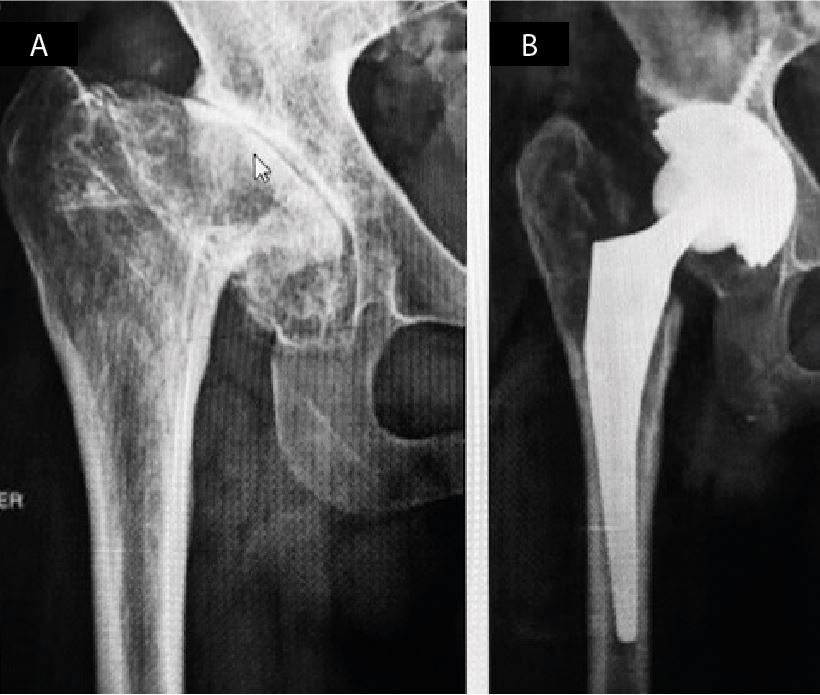

definition of quiescent septic arthritis is reserved for patients with a history of acute septic arthritis, who have completed antibiotic treatment, have normal laboratory values and absence of clinical signs that suggest ongoing infection. These patients present clinical and/or radiological signs of articular damage (Figure 2) that require joint replacement.

Group 2 includes patients with a history of previous septic hip arthritis and considered in remission of infection (13 hips in 12 patients). These patients were free of infection for at least two years since the end of treatment, had normal laboratory values and favourable clinical outcome. In them, one stage arthroplasty was performed, using the usual antibiotic prophylaxis scheme as for primary hips (1/2 gr IV cefazolin at anaesthetic induction and during the first 24 hours after surgery). All femoral heads were sent to culture. No previous joint aspiration was performed since, as described by Bauer et al (3), it serves no purpose in detecting eventual persistent infections of low virulence in quiescent septic arthritis, which explains the high number of false negatives reported by the authors (Figure 2 A and B). In our protocol, we do not consider the use of postoperative antibiotic schemes different from the primary hip protocol.